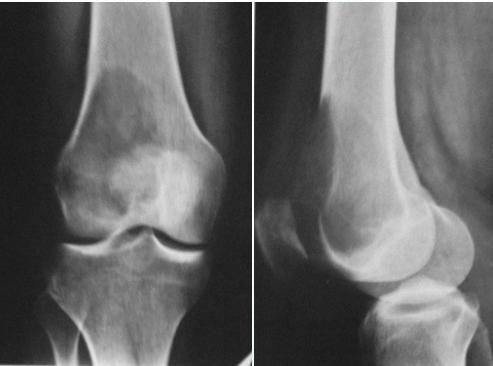

Giant-Cell Tumor

- Unknown origin:

- Giant cells abundant

- Behavior:

- One third benign

- One third locally aggressive

- One third (less) with distant metastasis

- Young adults

- Common sites:

- Around knee

- Proximal humerus

- Distal radius

Radiological Features

- Eccentric lesion:

- Radiolucent

- Soap bubble

- Abuts (adjacent) against the joint

- Thin cortex

- Margins may be clear / unclear:

- Depends on aggressiveness

- Treatment:

- Curettage & bone grafting

- More wide excision in recurrent and aggressive lesions

Source: Bone Tumors A Practical Guide to Imaging

Comparison of Cyst-Like Lesions in Bone

- After fusion of physis

- Extend to sub-articular